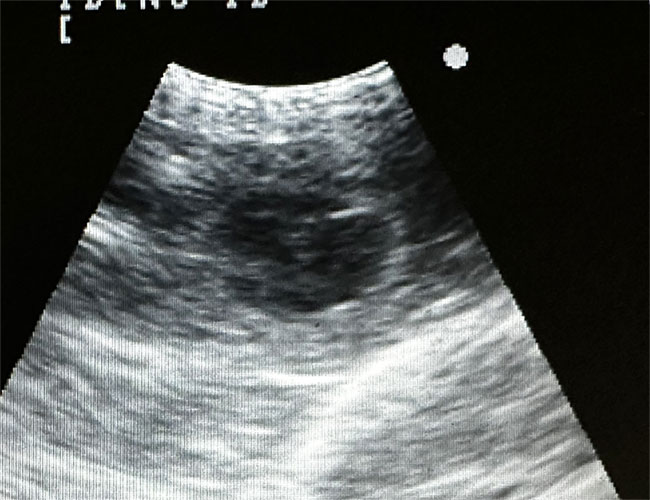

Riassunto degli esami radiografici dell'anca (HD) e dei gomiti (ED) nei cuccioli provenienti dal mio allevamento.

Il mio lavoro non sarebbe possibile senza il sostegno e la collaborazione dei proprietari dei miei cuccioli. Sottoporre i cani all’esame radiografico ufficiale per la displasia dell’anca e del gomito è un gesto importante e di grande valore. A tutti voi che con impegno e fiducia sostenete il mio lavoro va la mia sincera e profonda gratitudine.